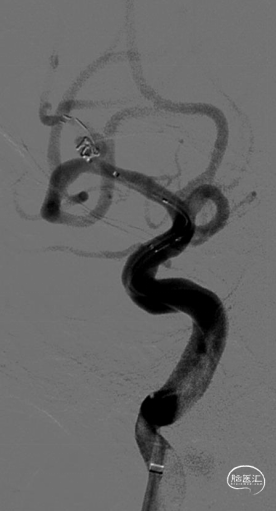

使用SL-10 微导管在Synchro 微导丝引导下分别进入载瘤动脉及动脉瘤腔内。

采取半释放法于上干释放3*21mm Altas支架1枚,同时于动脉瘤内填塞弹簧圈至致密。

最后全释放支架,序贯撤出微导管,造影可见支架打开完全、贴壁完美,载瘤动脉角度变化小,管腔通畅,动脉瘤Raymond 1级栓塞。